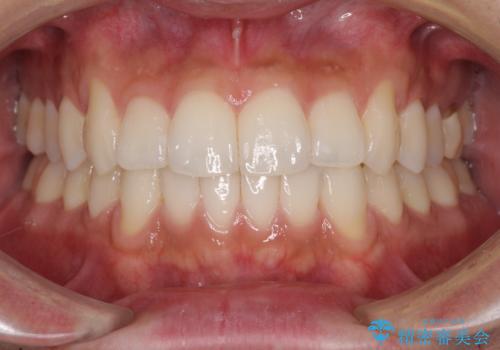

前歯のデコボコを治したい インビザライン矯正治療

- 前歯のデコボコを治したいとのことで来院された患者様です。

上下顎ともに歯列全体の後方移動とIPR(歯と歯の間を削る)によってデコボコが解消するように設計し、インビザラインにより治療を行うこととしました。

毎日22時間以上しっかりとマウスピースを装着していただいたので、スムーズに治療が進みました。歯と歯の間を削ることでうまくスペースコントロールでき、1年強で終えることができました。